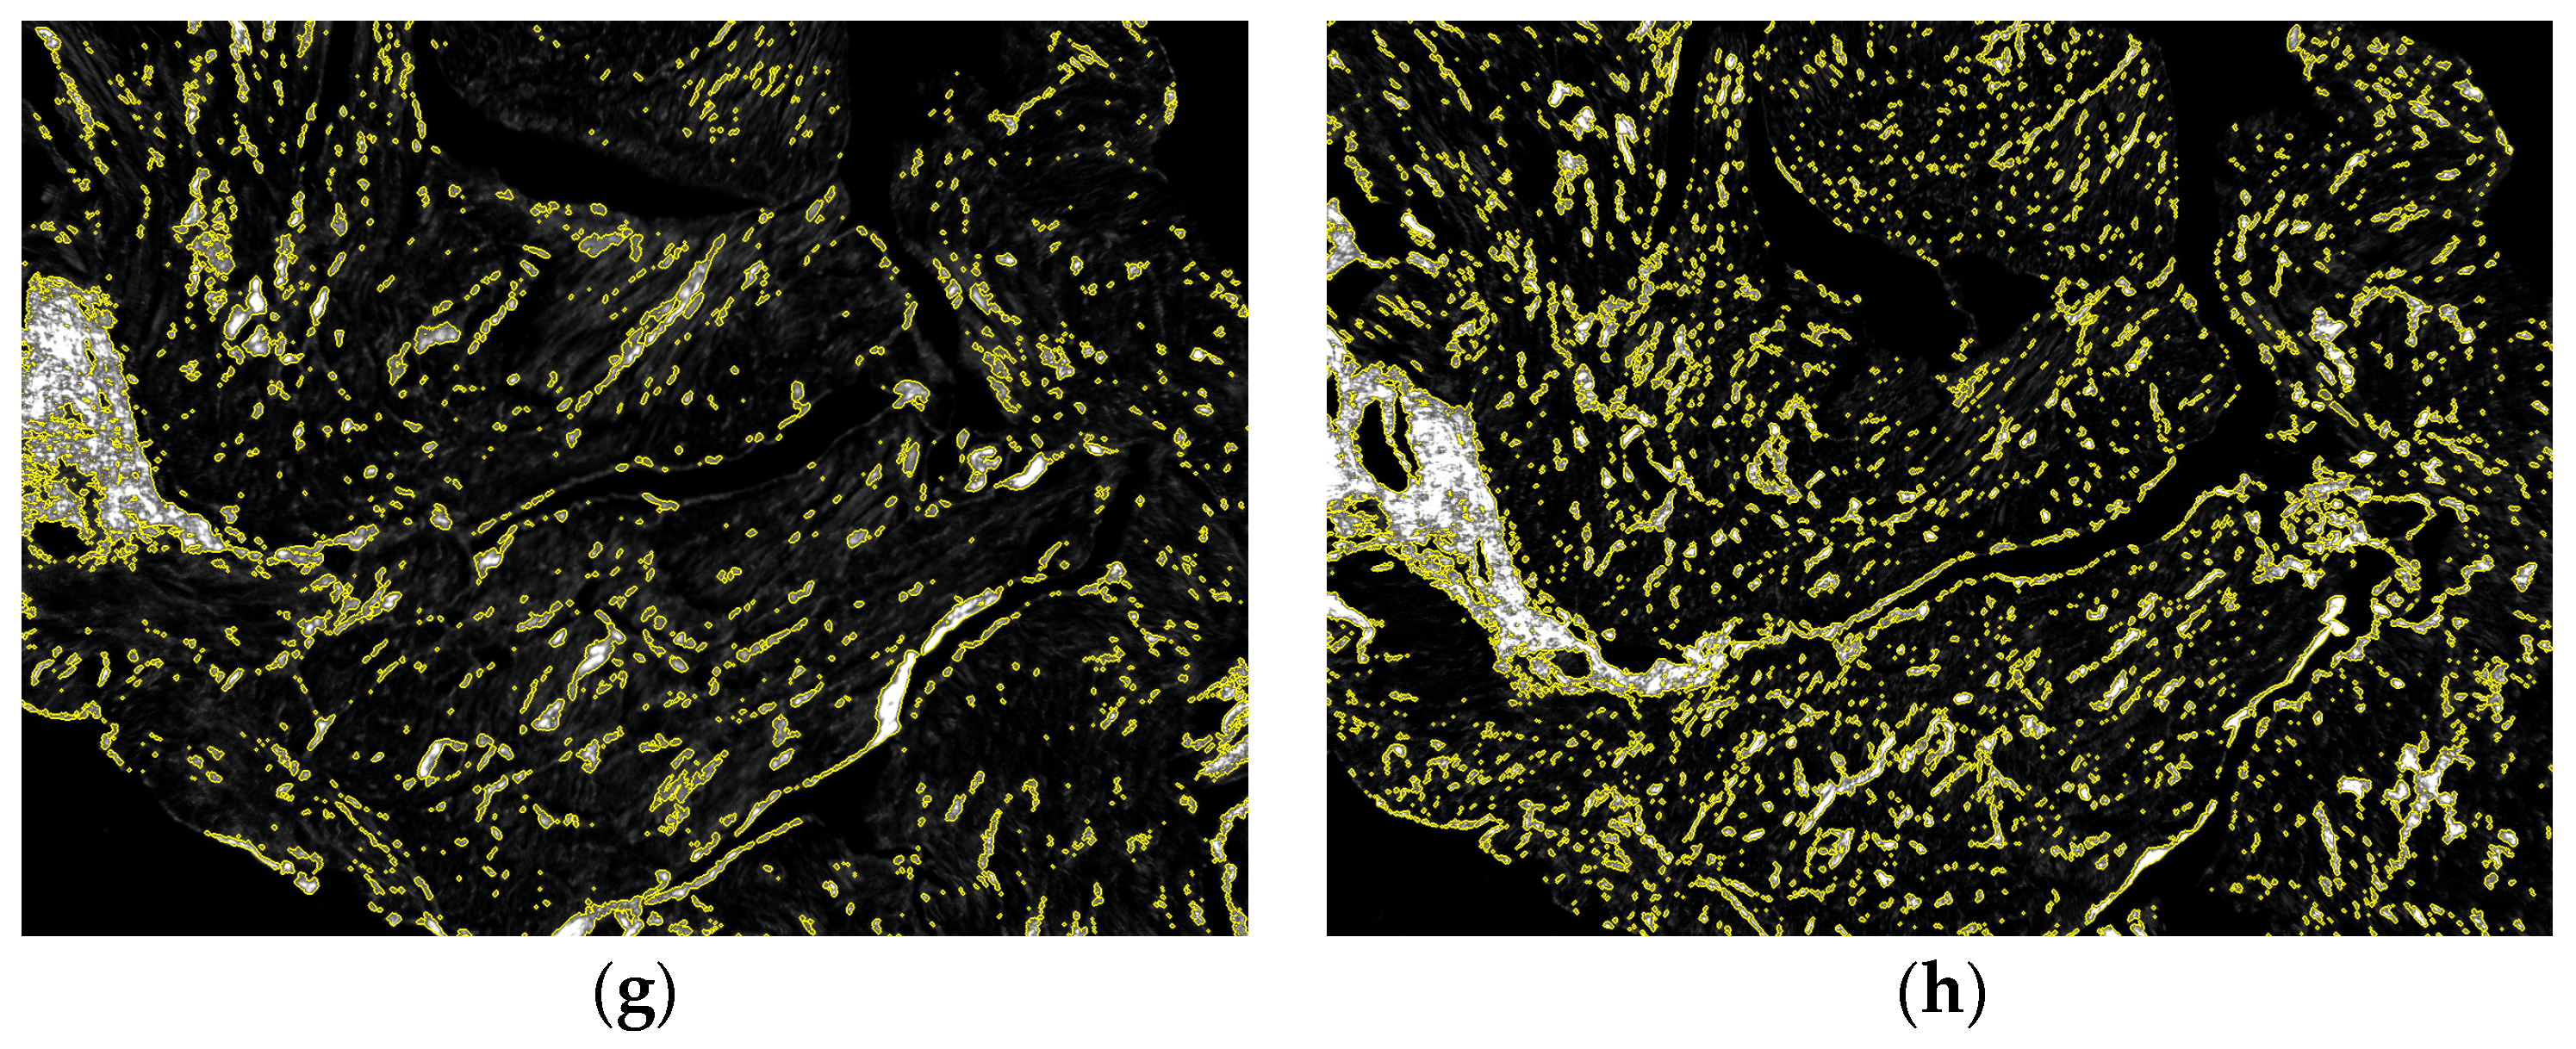

3.2. Birefringence Analysis and Collagen Fraction Quantification

3.3. Proof of Concept Application of the Framework for the Quantification of Cardiac Fibrosis